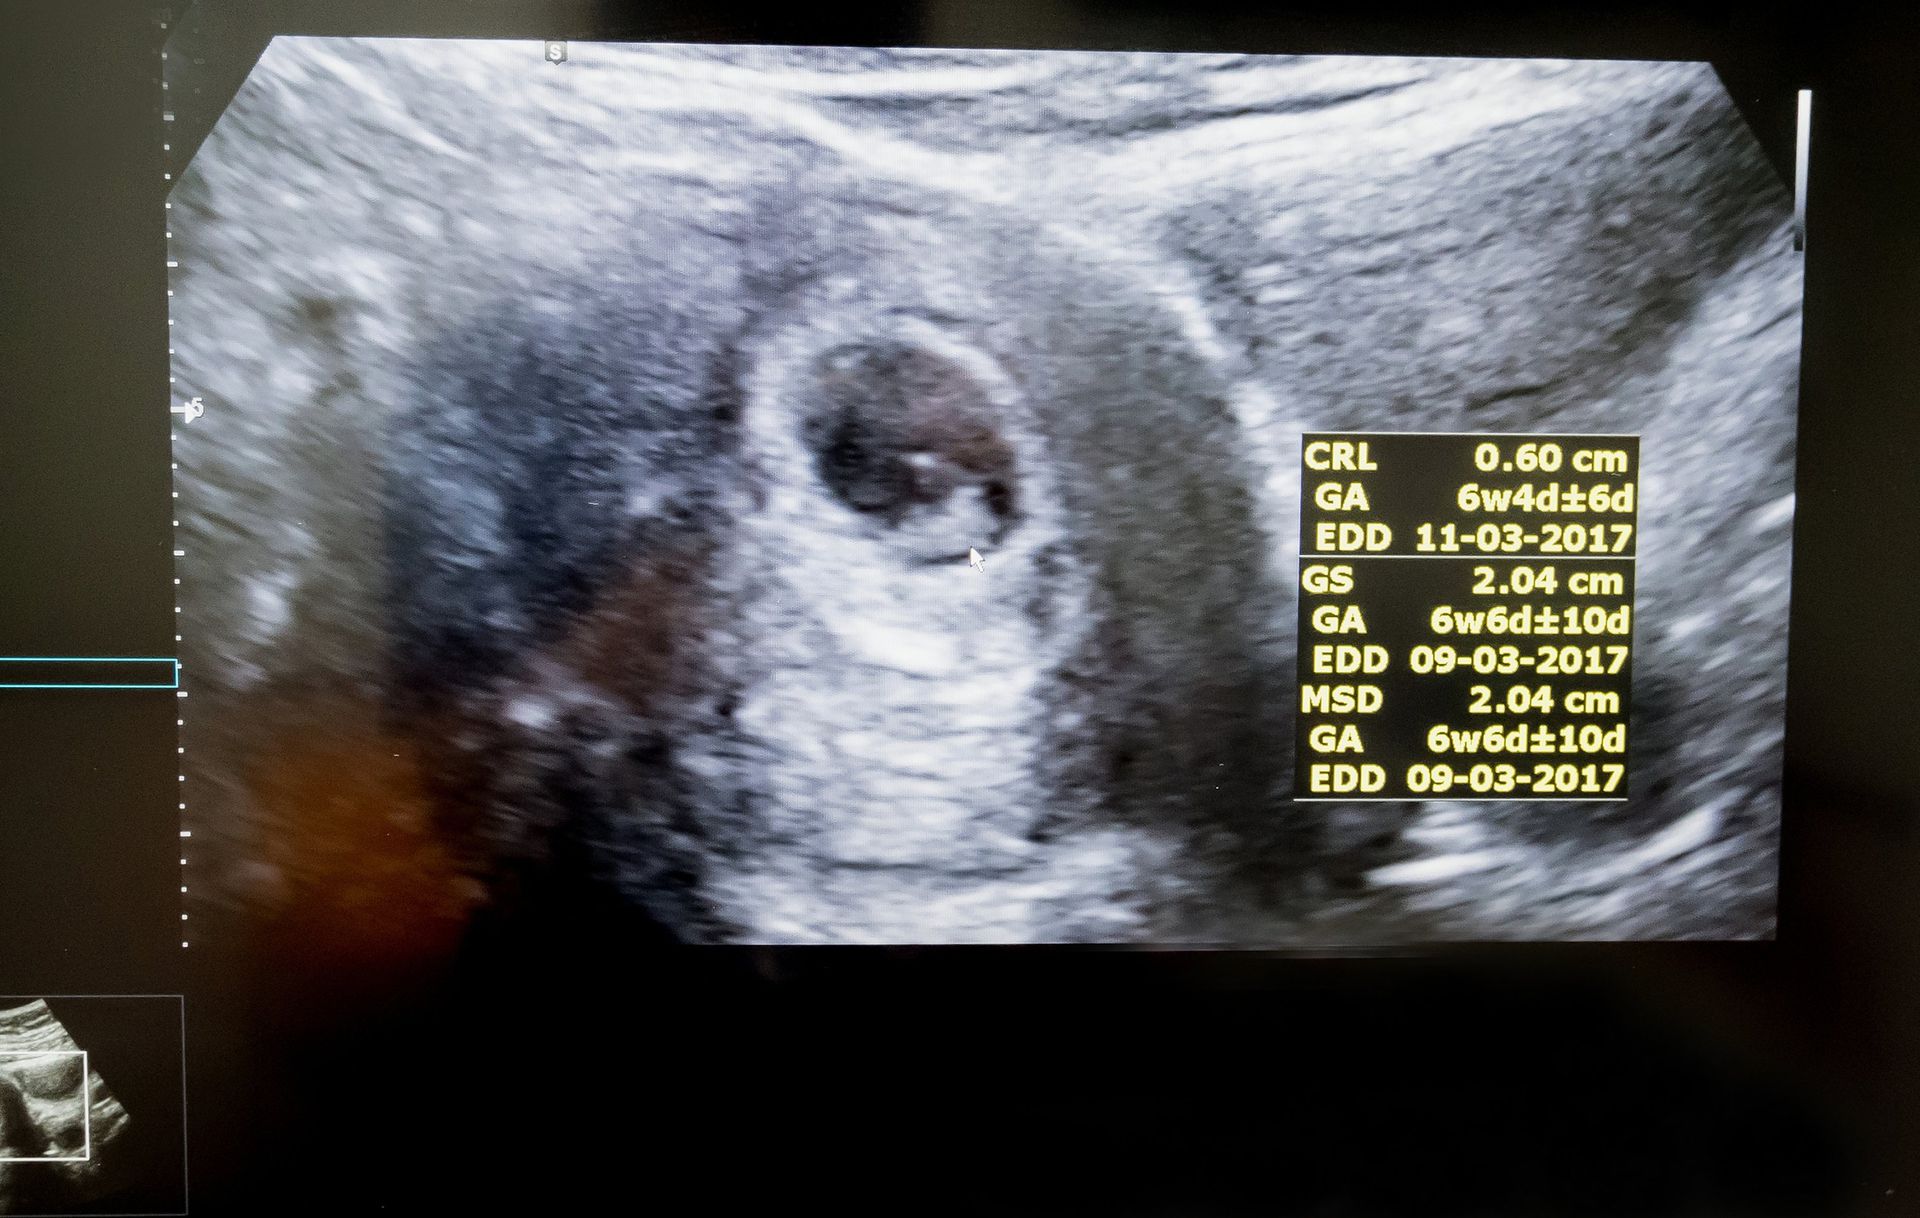

Узи 6 недель нет сердцебиения

Узи 6 недель нет сердцебиения 119 фотографий